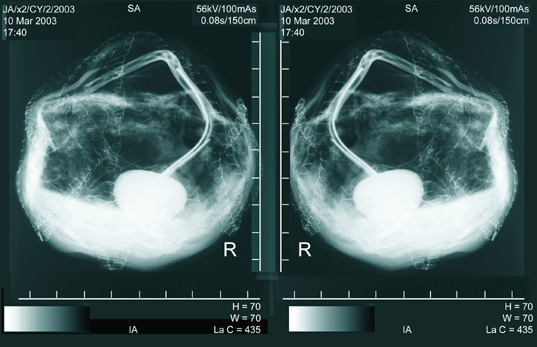

X-ray - Cyst 1